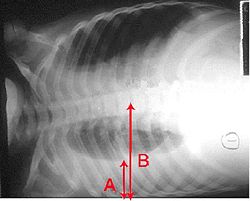

Pleural effusion, empyema, and abscess

Occasionally, microorganisms infecting the lung will cause fluid (a pleural effusion) to build up in the space that surrounds the lung (the pleural cavity). If the microorganisms themselves are present in the pleural cavity, the fluid collection is called an empyema. When pleural fluid is present in a person with pneumonia, the fluid can often be collected with a needle ( thoracentesis) and examined. Depending on the results of this examination, complete drainage of the fluid may be necessary, often requiring a chest tube. In severe cases of empyema, surgery may be needed. If the fluid is not drained, the infection may persist, because antibiotics do not penetrate well into the pleural cavity.

Rarely, bacteria in the lung will form a pocket of infected fluid called an abscess. Lung abscesses can usually be seen with a chest x-ray or chest CT scan. Abscesses typically occur in aspiration pneumonia and often contain several types of bacteria. Antibiotics are usually adequate to treat a lung abscess, but sometimes the abscess must be drained by a surgeon or radiologist.